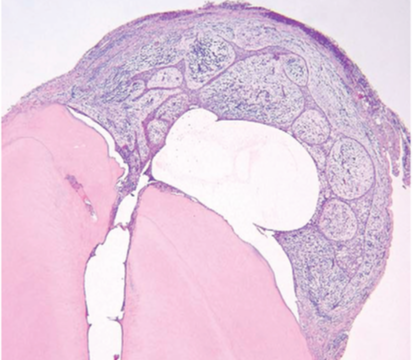

Chronic Hyperplastic Pulpitis

(Instead of inflammation going out the apex, it goes out the crown)